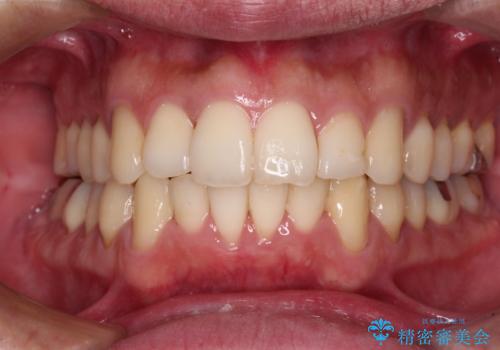

下顎骨が顕著に右側にずれている インビザラインによる咬合改善

最終的にはゴムかけなどを活用して改善することができましたが、4年近い治療期間を要することとなりました。